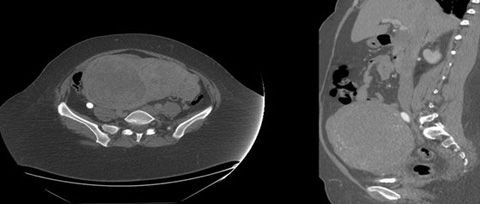

Because of the immediate recurrence of thrombosis in the context of normal coagulation parameters, a CT scan of the abdomen was ordered to evaluate possible mechanical causes or venous stasis.

Figure 4

Abdominal CT demonstrated a large pelvic mass measuring 12.6 x 18.3 x 16.4 cm (Figure 3). The mass appeared to compress the IVC at the iliac bifurcation, exerting a mass effect on the right ureter that, in turn, resulted in right hydroureter with mild hydronephrosis (Figure 4).